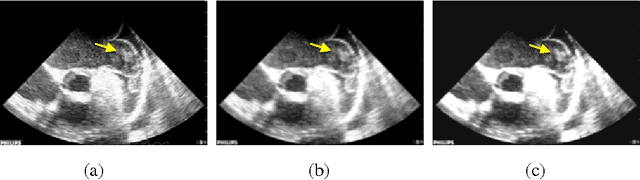

Abstract:Transesophageal echocardiography (TEE) is widely used to detect left atrium (LA)/left atrial appendage (LAA) thrombi. In this paper, the local binary pattern variance (LBPV) features are extracted from region of interest (ROI). And the dynamic features are formed by using the information of its neighbor frames in the sequence. The sequence is viewed as a bag, and the images in the sequence are considered as the instances. Multiple-instance learning (MIL) method is employed to solve the LAA thrombi detection. The experimental results show that the proposed method can achieve better performance than that by using other methods.